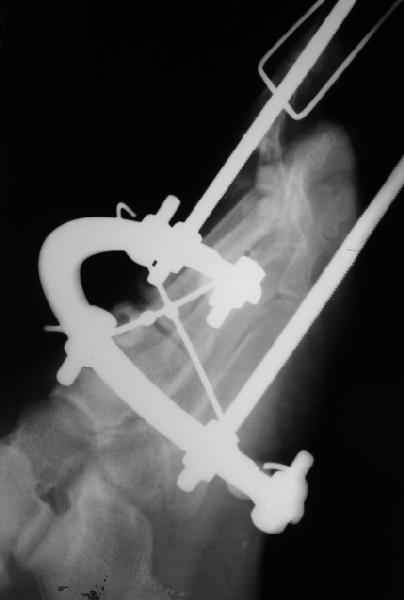

1 передний отдел стопы делается в косой, а не боковой проекции - на боковой все плюсневые кости накладываются друг на друга, и ничего не видно - это же аксиоматично! Я, например, на прямых проекциях не вижу совсем признаков перелома первой и четвертой плюсневой, и сомневаюсь в переломе третьей, боковые же совершенно неинформативны.

Они же наложили дистракционный аппарат (вместо того, чтоб сделать открытое вправление зафиксировать это одной спицой Киршнера), продержали больного две недели в аппарате (ЗАЧЕМ?), а теперь спрашивают , что делать...

Вы говорите "Да, снимки не лучшие, но суть проблемы на них видна ведь."

Как же суть проблемы видна? Человек говорит о переломе первой (то есть речь идет о переломо-вывихе?), второй, третьей и четвертой плюсневых костей, а я вижу только перелом второй. мне кажется, что проблема в таком случае будет чуть-чуть другая. Кстати, сколько переломов насчитали на этих снимках Вы?

Имеем - без малого двухмесячные переломовывихи перeднего отдела стопы , больной в отделении 20 дней, доктор думает, что ему делать:

Та же проблема - по крайней мере на снимке в аппарате (фас) отчетливо видно перелом ее головки.

3 кстати, Вы перелом пкрвой плюсневой видите? В каком месте и на каком снимке?

Вот головка более прицельно.